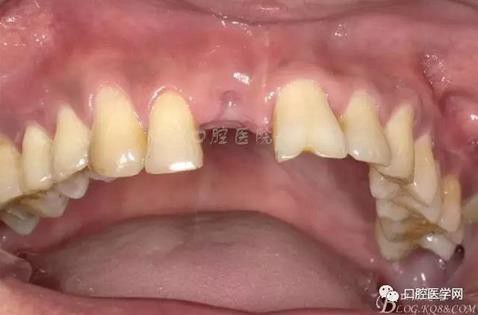

圖4 術(shù)前正位頜面照